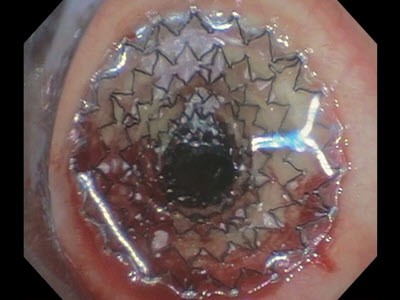

The AERO Fully Covered Tracheobronchial Stent is delivered to the target site by means of a proprietary, flexible, over-the-wire delivery system.

The AEROmini Fully Covered Tracheobronchial Stent builds on the strengths of the original AERO platform. The stent is delivered to the target site by means of an optimized low profile, through-the-scope or over-the-wire delivery system.

AERO DV promotes accurate placement under direct bronchoscopic visualization without the need for fluoroscopic or wire guidance.